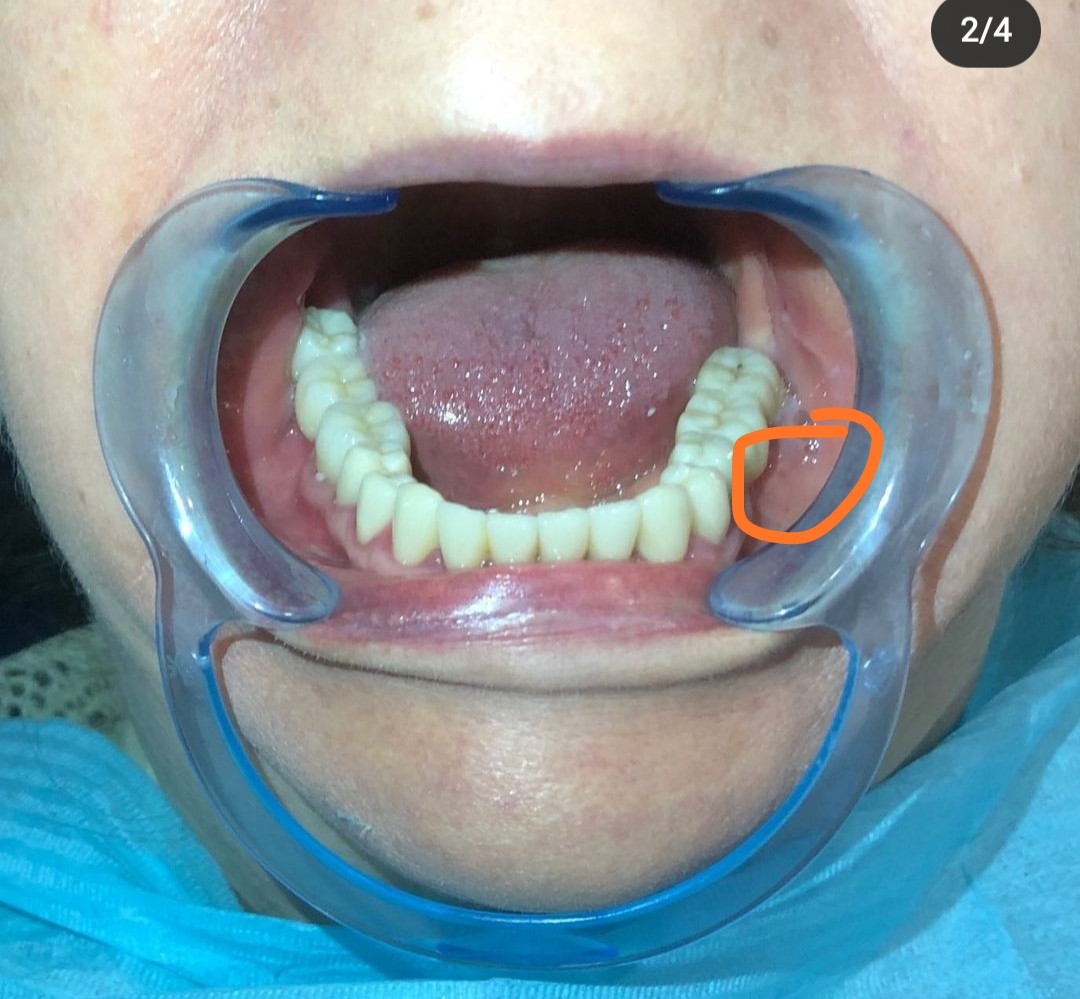

Здравствуйте. Прошу помочь советом. 4 дня назад впервые в жизни удалил зуб. Нижний, предпоследний в ряду, жевательный. Врач назначил его удаление еще полгода назад, но я не спешил, и удалил его сейчас в срочном порядке, так как образовался флюс. Анестезию кололи платную, и по максимуму, для лучшего эффекта - очень боюсь зубной боли. Удаление прошло относительно легко и успешно, десну не резали и не шили. Дырка со сгустком заживает хорошо, десна не болит, я соблюдаю все рекомендации - ем исключительно на другой стороне, ванночки сода/соль, кора дуба, ромашка, прыскаю мирамистин. Но проблема в том, что со второго дня после удаления очень сильно болит щека, боль в основном пульсирующая. Щека еле заметно припухла - в передней нижней части, недалеко от уголка рта, хотя удаленный зуб сзади. Боль обостряется при мимике, улыбке, приеме пищи. Пил обезболивающее - на день помогало. Сегодня боль утихла - пить ничего не стал. Легкая пульсация только. Вчера обнаружил увеличение лимфоузлов под челюстью в задней части. Опять же, не заметно зрительно, а прощупыванием, лимфоузел не болит, просто я его ощущаю. Насчет припухлости щеки - не знаю, может тоже лимфоузлы в щеке воспалились - есть они в щеке? Подскажите, может все это быть связано с удалением вроде несложного зуба? Считается это нормой? Может это быть от уколов анестезии? Надо ли как то лечить увеличенные лимфоузлы, или само пройдет?

Доктор добрый вечер, тоже самое и в меня заметил два месяца назад, увеличен лимфоузел 8.5-5 мм. Там же на челюсти. С внутренней стороны вообще ничего не заметно не прошупывается только снаружи если прощупать. Ещё 6 месяцев назад удалили зуб мудрости с этой стороны. Ставил капельницы ципифин 7 дней не ушло. Уплотнение мягкое подвижное безболезненное мне 30 лет